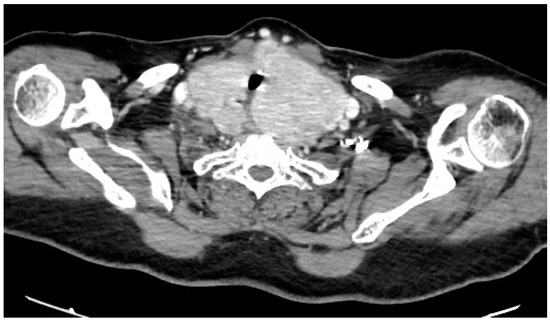

The Resolution of Obstructive Sleep Apnea in a Patient with Goiter after Total Thyroidectomy: A Case Report

2. Case Description